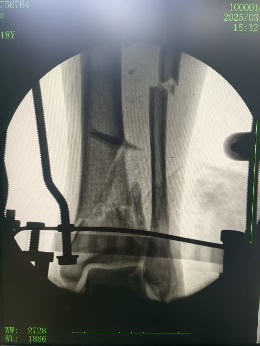

六軸機器人輔助下腓骨穿針